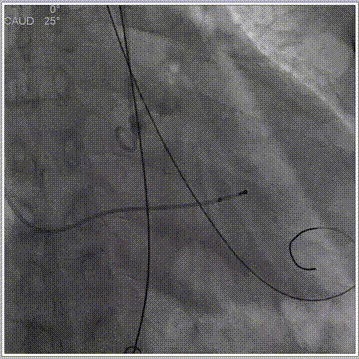

• 预装AV31瓣膜,瓣环下2mm定位释放,释放角度LAO 0° CAU 25°(左右重合)左右,释放后调整至左冠切线位LAO 35° CRA 9°左右进一步评估冠脉灌注、瓣膜稳定性及展开形态后释放。

主动脉根部造影

释放工作位评估

• RAO 1° CAU 19°(右窦中心) 左右跨瓣。

• 预装AV31瓣膜,瓣环下2mm定位释放,释放角度RAO27° CAU 37°(左右重合)左右,释放后调整至左冠切线位LAO 15° CRA 8°左右进一步评估冠脉灌注、瓣膜稳定性及展开形态后释放。